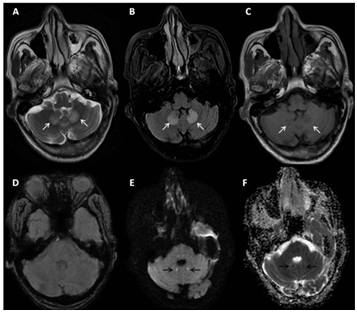

A sixty five-year-old male, diagnosed as a case of non-alcoholic steato-hepatitis related compensated chronic liver disease since one year, presented to us with complaints of progressive non cholestatic jaundice without prodrome for a period of 20 days. This was followed by painless abdominal distension and decreased urine output. The patient subsequently developed altered sensorium in a period of two days associated with excessive drowsiness along with high grade fever. He was teetotaller with history of type II diabetes since 12 years and had no other co-morbidities .There was no history of blood transfusions, alternative medicine intake. He was intubated outside and shifted to us on ventilator and inotropic support. Labs results showed haemoglobin 9.6 g/dL, white blood cell 27880/mm3 ,platelet 98000/mm3, BUN 93 mg/dL ,serum creatinine 4.01mg/dL ,severe metabolic acidosis with arterial lactate of 4.5 mmol/L. Liver function tests showed AST 40 U/L, ALT 32 U/L, alkaline phosphatase 129 U/L, GGT 45 U/L and bilirubin of 1.18 mg/dl. PT INR was 4.5 with very low fibrinogen. Acute viral markers (hepatitis A & E) and hepatitis B and C serology were negative, malaria antigen and leptospira IgM were nonreactive. Autoimmune markers were negative. Ultrasonography(USG) showed features of liver cirrhosis with portal hypertension. It also showed ill-marginated ill-defined subtle hypoechoic lesion in superior segment of right lobe with hypoechoic thrombus in right hepatic vein protruding into the inferior vena cava (Patients had been regularly following and his USG 3 months ago did not show any SOL). Ascitic fluid white cell count (842 cells/dL) with 72% neutrophils suggested spontaneous bacterial peritonitis. The α-fetoprotein level was 82 ng/mL. CA 19-9 and CEA were normal. Continuous renorenal replacement was initiated along with aggressive medical management for metabolic acidosis and hemodynamic instability. Contrast CT scan confirmed liver cirrhosis, gross ascites and splenomegaly (Figure 1) it also revealed a hypo-dense, ill-marginated, non-enhancing, sub-capsular mass in segment VII and VIII with non-enhancing, occlusive skip thrombi in the right hepatic vein protruding into IVC, occlusive thrombus of the right and main portal veins protruding into the left portal vein and retro-pancreatic splenic vein. Multiple enlarged necrotic pre-vascular, anterior peridiaphragmatic and pericardial lymph-nodes were also seen (Figure 2). In view of coagulopathy ,hemodynamic instability and cirrhosis it was decided to do the internal mammary lymph node after TEG based correction of coagulopathy . It showed (Figure 3) cells with biphasic neoplasm with epithelioid and spindle cells, marked nuclear pleomorphism with giant and bizarre nuclei and a high Ki-67 index. IHC showed strong coexpression of PanCK and Vimentin and was negative for LCA, CK7, CK20, TTF1, Hep Par-1, Glypican 3, p40. These features were suggestive metastatic PHSC. Meanwhile patient’s condition rapidly worsened over period of 5 days with development of multi organ failure. He eventually succumbed on the seventh day of hospital stay.

Figure 3 cells with biphasic neoplasm with epithelioid and spindle cells, marked nuclear pleomorphism with giant and bizarre nuclei and a high Ki-67 index.